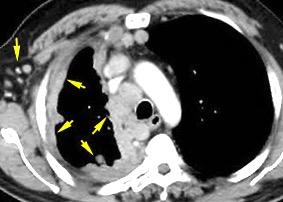

40. EMPIEMA PLEURAL. ORIGEN HEPÁTICO